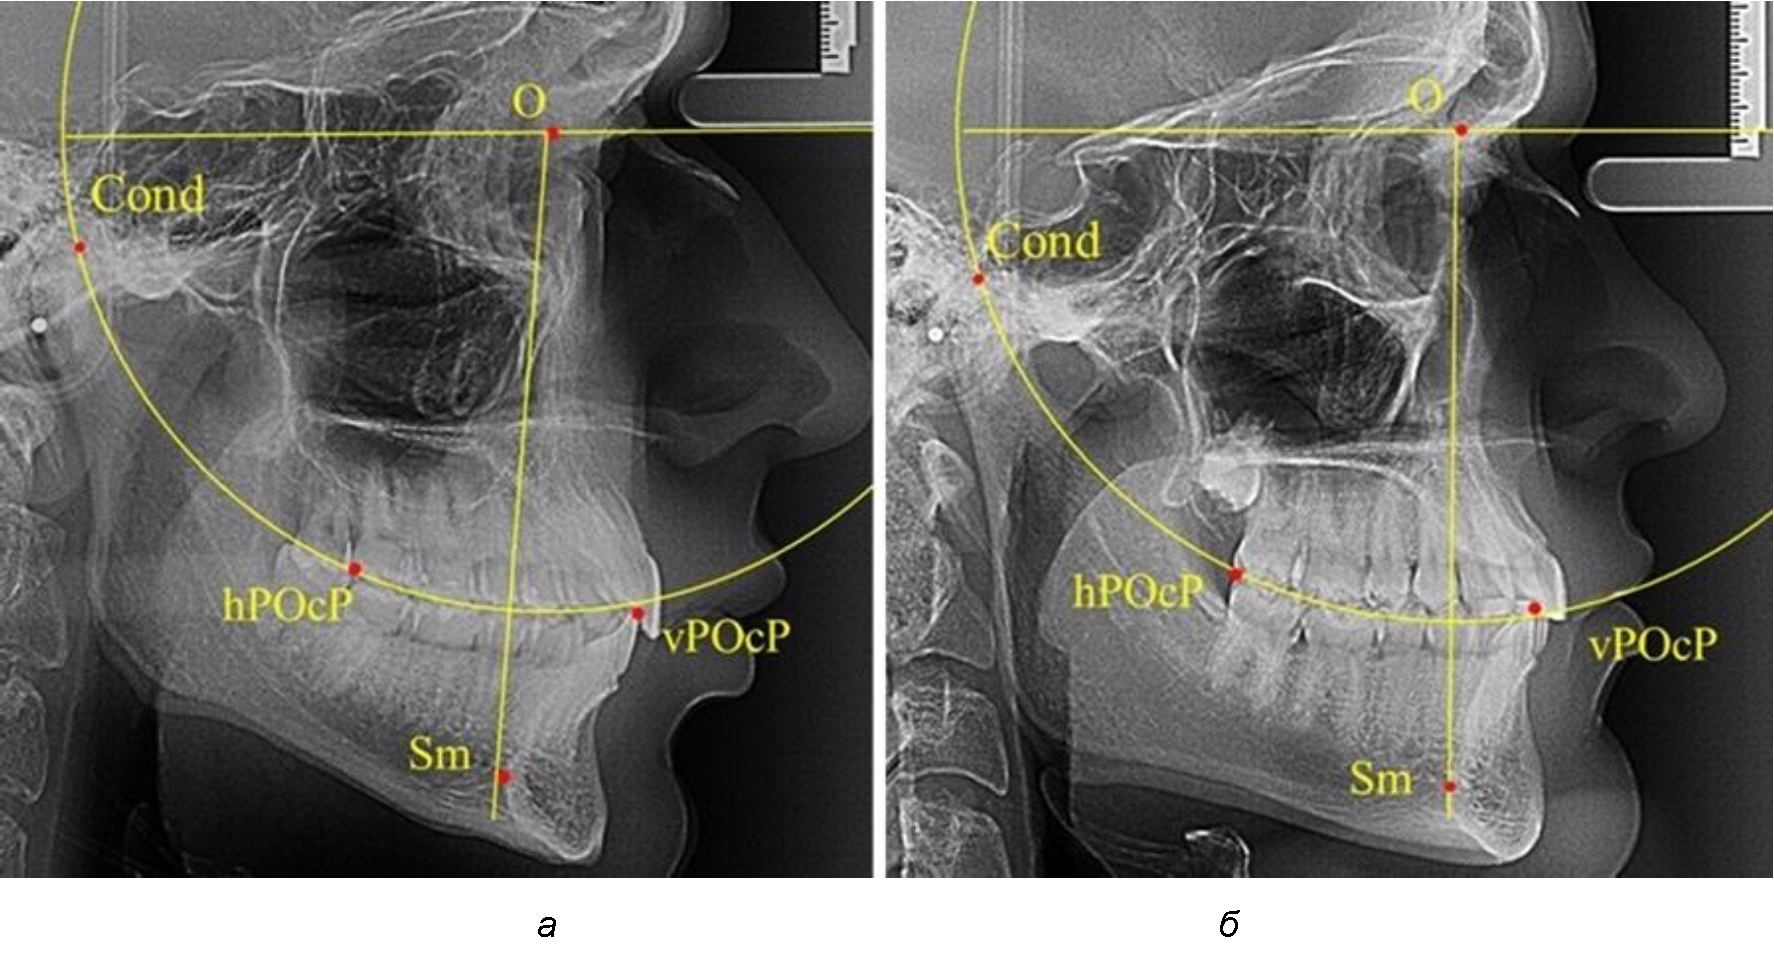

Анализ снимков проводили с использованием традиционного построения стресс-оси по Bimler. Для удобства построения использовали компьютерную программу PowerPoint. Основными точками для построения круга были передняя (vPOcP) и дистальная (hPOcP) окклюзионные точки, а также верхняя выпуклость суставной головки (Cond).

Вставка из программы в виде овала накладывалась на фотографию рентгенограммы и ручным способом растягивалась так, чтобы получился круг, проходящий через обозначенные реперные точки.

Центр окружности О, соединяющей точку резцового перекрытия с жевательной поверхностью зубов и серединой суставных головок, соединяли с выступающей точкой Sm на внутреннем контуре подбородка (рис. 1).

Рис. 1. Метод анализа ТРГ по Bimler

Результаты исследования рентгенограмм с мезотрузионным типом резцов показали, что линия Bimler проходила позади первых премоляров у людей с широким типом подбородочного выступа, однако окклюзия была физиологической и не требовала удаления премоляров, что носило рекомендательный характер при проведении подобных исследований при аномалиях прикуса. У людей со средними формами подбородочного выступа линия Bimler проходила впереди первых премоляров (рис. 2).

Аналогичная ситуация была у людей и с узкими вариантами подбородочного выступа.

Таким образом, при мезотрузионном типе зубочелюстных дуг расположение премоляра впереди линии Bimler при широких вариантах подбородка не может быть критерием выбора экстракционных методов лечения.

Рис. 2. Положение первых верхних премоляров при мезотрузии с широкими (а) и средними (б) размерами подбородка